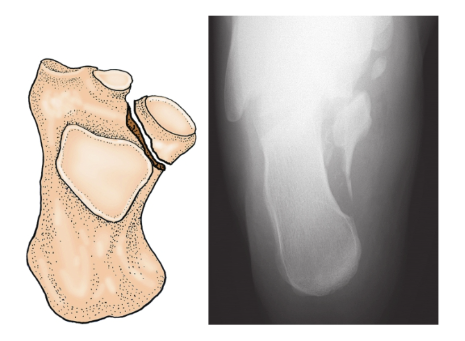

4、跟骨载距突骨折:

足内翻位时,载距突受到距骨内下方冲击而引起,极少见。一般移位不多,如有移位可用[插图]指将其推归原位,用短腿石膏固定4~6周(图9)。

图9 载距突骨折